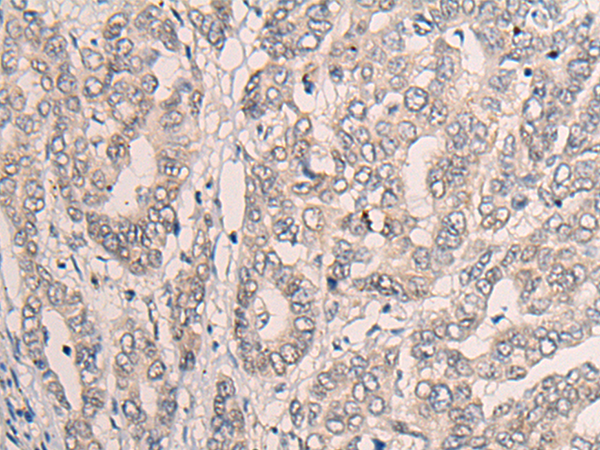

IHC positive control: |

Human liver cancer |